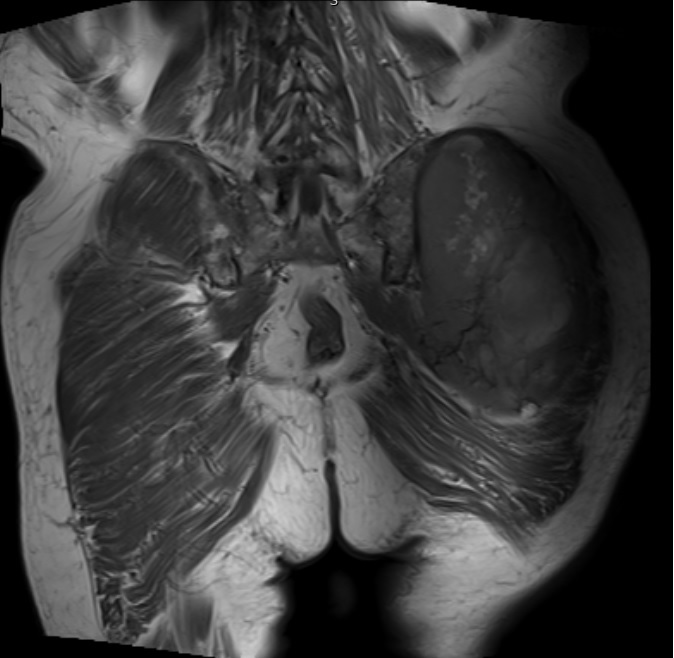

• Large encapsulated lipomatous mass with multiple thick internal trabeculations. (Fig. 1 – 13)

• Signal loss on FS T1 weighted images, and focal nodules(>1 cm is suggestive of a DDLS). (Fig. 1 & 7)

Fig. 1 & 2 Magnetic Resonance Image shows a large heterogeneous mass in the left gluteal region with low intensity signal on Axial (Fig. 1) and Coronal (Fig. 2) T1-weighted images admixed with some high signal areas indicative of fatty tissue. Higher intensity signal is visible compatible with hemorrhage or necrotic tissue. The mass involve the central portion of the left iliac bone.